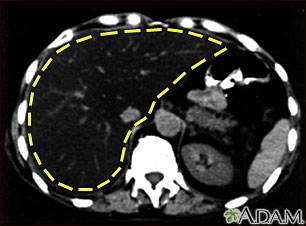

Enlarged liver refers to swelling of the liver beyond its normal size. Hepatomegaly is another word to describe this problem.

If both the liver and spleen are enlarged, it is called hepatosplenomegaly.

- Abdominal x-ray

- Abdominal ultrasound (may be done to confirm the condition if the provider thinks your liver feels enlarged during a physical exam)

- CT scan of the abdomen

- MRI scan of the abdomen